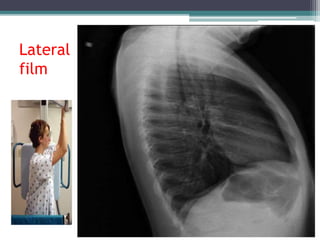

Lateral

film

Radiography • Different viewsof the chest can be obtained by changing the relative orientation of the body and the direction of the x -ray beams: • The most common views are: 1. Posteroanterior view (PA); 2. Anteroposterior view (AP); 3. Lateral